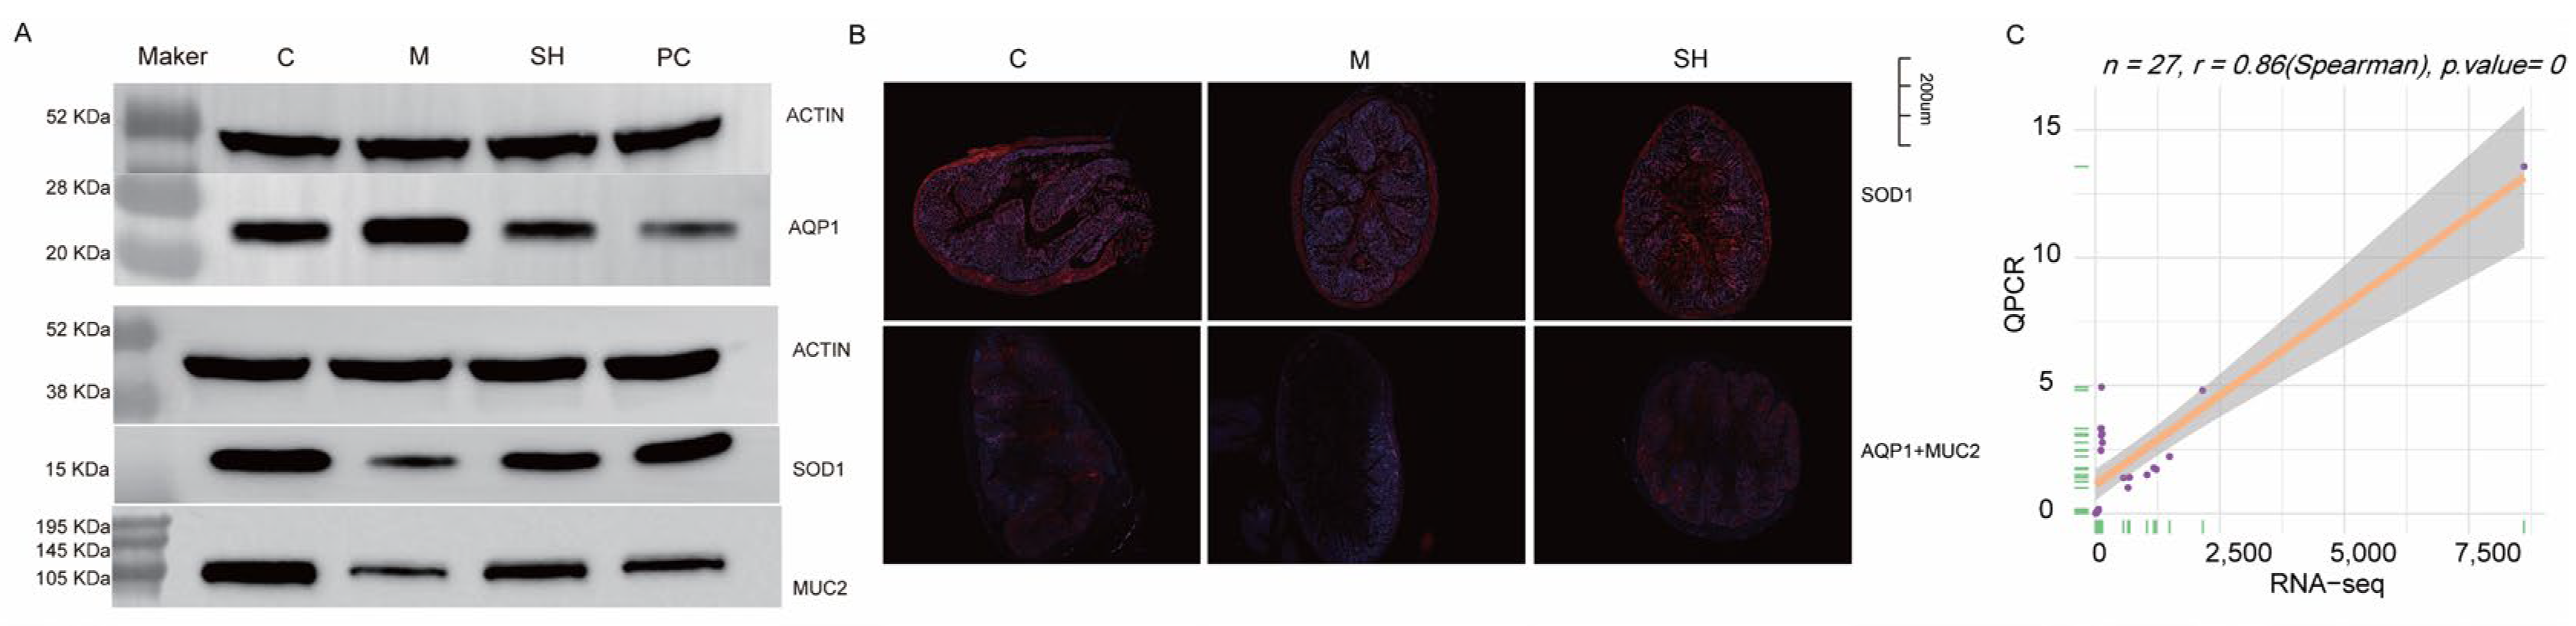

2.9. SH Inhibited AQP1 Expression and Promoted SOD1 and MUC2 Expression